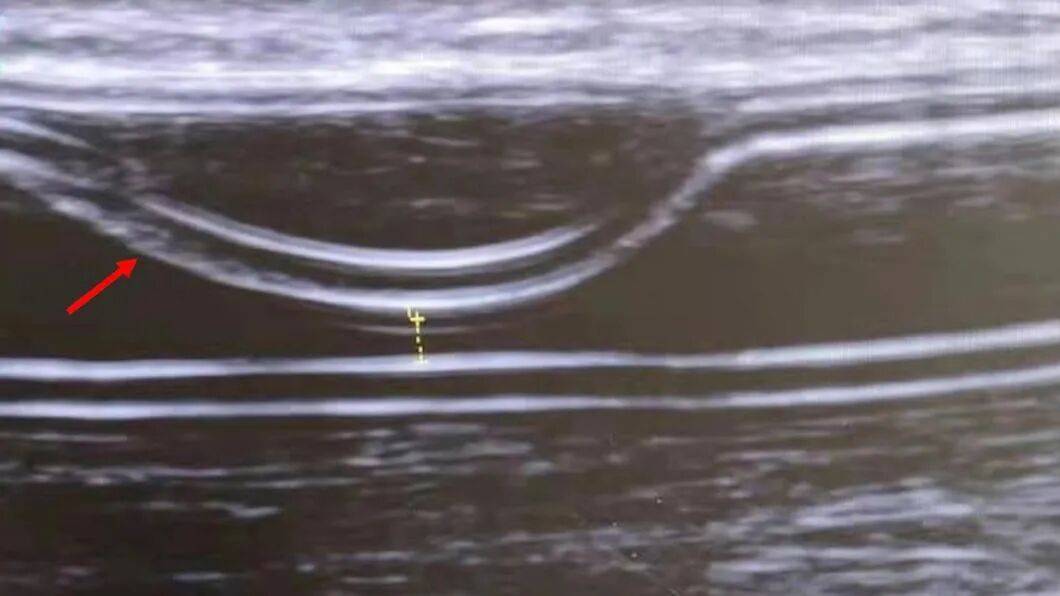

本研究對即穿型人工血管夾層的特點與處理最新研究進展進行了綜述論文。作者在PubMed 資料庫中進行檢索,共發現7 例病例報告和 1 項佇列研究,對其進行總結分析後發現:(1)早期插管動靜脈移植物夾層的診斷主要依靠多普勒超聲檢查。(2)大多數報道的病例涉及 Acuseal 移植物,夾層主要位於中膜和外膜之間,且多在前壁。其可能與球囊擴張、血管鞘插入、不適當的穿刺角度以及反覆的關節活動有關。(3)目前尚無標準的治療方案。可用的治療選擇包括經皮腔內血管成形術、支架植入、移植物置換和保守觀察。移植物置換的初始通暢率最佳,其次為支架植入。建議將支架植入或移植物置換作為一線治療方法。

圖3:即穿型人工血管夾層超聲圖

本研究的上述結果,為廣大血管外科及腎內科醫師,在處置即穿型人工血管夾層這一併發症上提供了臨床思路和指導意見論文。得到了《Hemodialysis International》審稿專家的高度評價。專家指出,本文是一篇關於即穿型人工血管夾層的重點綜述,揭示了一種臨床相關但未被廣泛認識到的併發症。作者對即穿型人工血管夾層發病率、機制特點和治療方案進行了更平衡的討論。現有證據的侷限性得到了適當的承認,文章非常有教育指導意義。